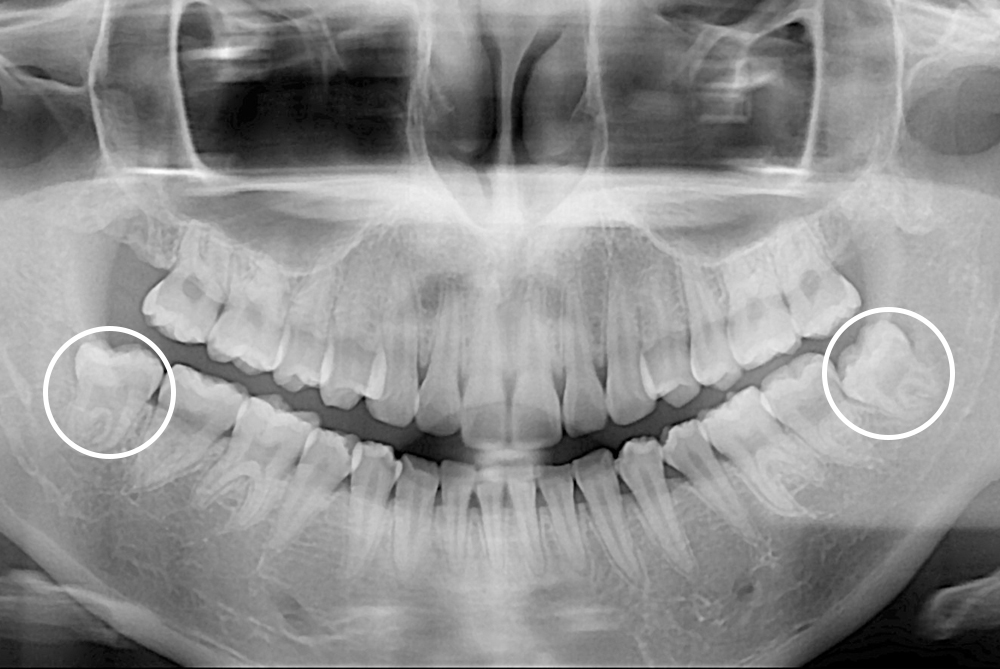

[사랑니] 매복 사랑니 발치

치료후 : 2021-02-27

세종치과는 구강악안면외과학 박사이신 원장님이 발치하는 치과입니다.